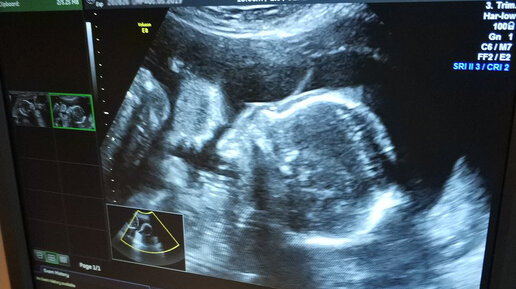

Прошло уже несколько месяцев со дня 2го скрининга и только сейчас я собралась с силами написать о тех днях. Надо было все осознать, принять и пережить. На скрининг я шла воодушевленная. Ведь по итогу 1 скрининга все риски сняли, меня заверили, что у ребенка все хорошо. Каких-то плохих предчувствий и мыслей не было. Сначала на узи все шло как обычно. Называли какие-то цифры и сверяли с табличными. Я услышала несколько раз фразу "кишечник повышенной эхогенности", почему-то подумала, что это про меня (и связано с сильным газообразованием) и не придала значения. А дальше началось. Оказывается по результатам 1 скрининга не все было так радужно...